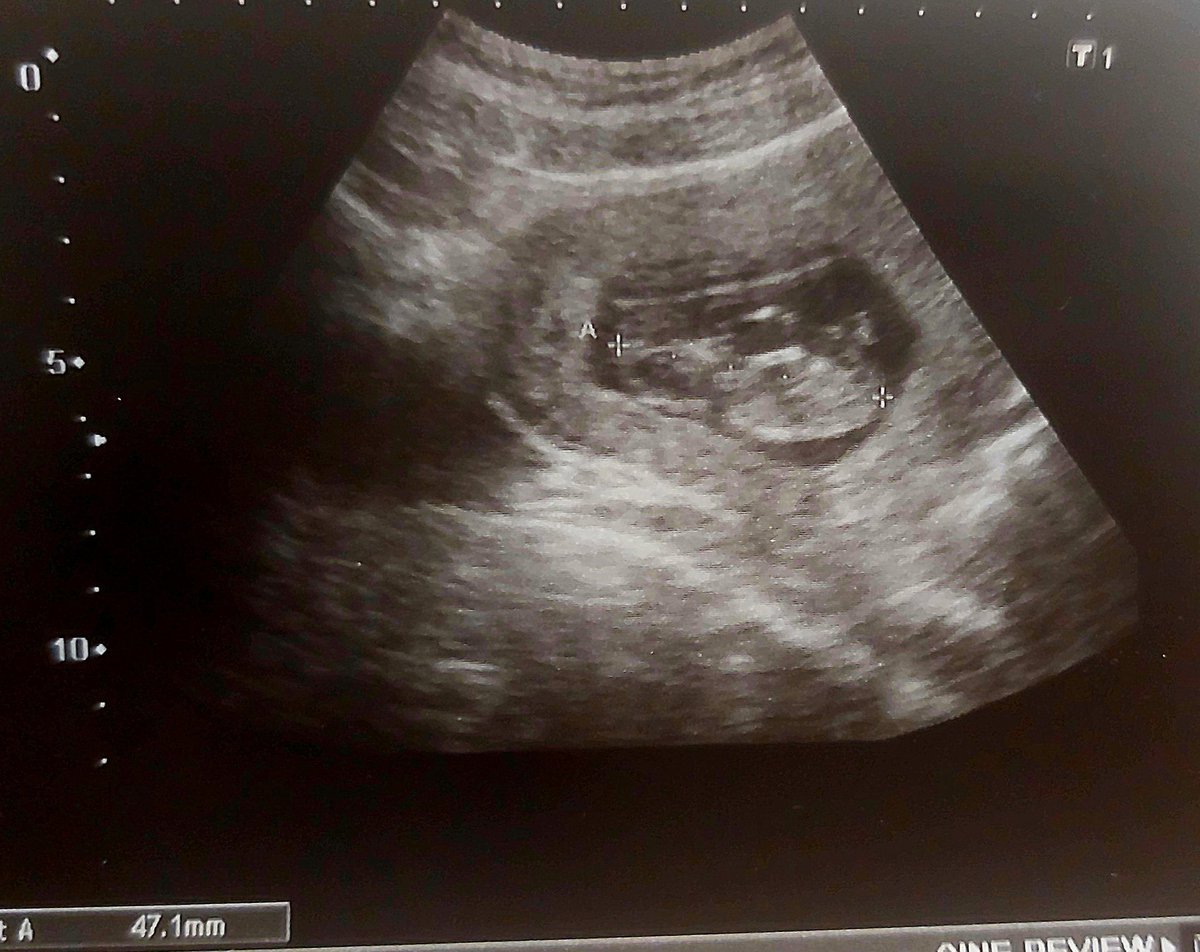

#infertilpreñis ayer tuve mi primera cita con obstetra y fue genial. La médico muy maja. Por primera vez me hicieron eco abdominal. 🦔 ha crecido mucho, ya mide 4,71 cm y se movía un montón!. Hoy he tenido el cribado y la semana que viene o la otra la eco de la 12.  Qué ilusión!